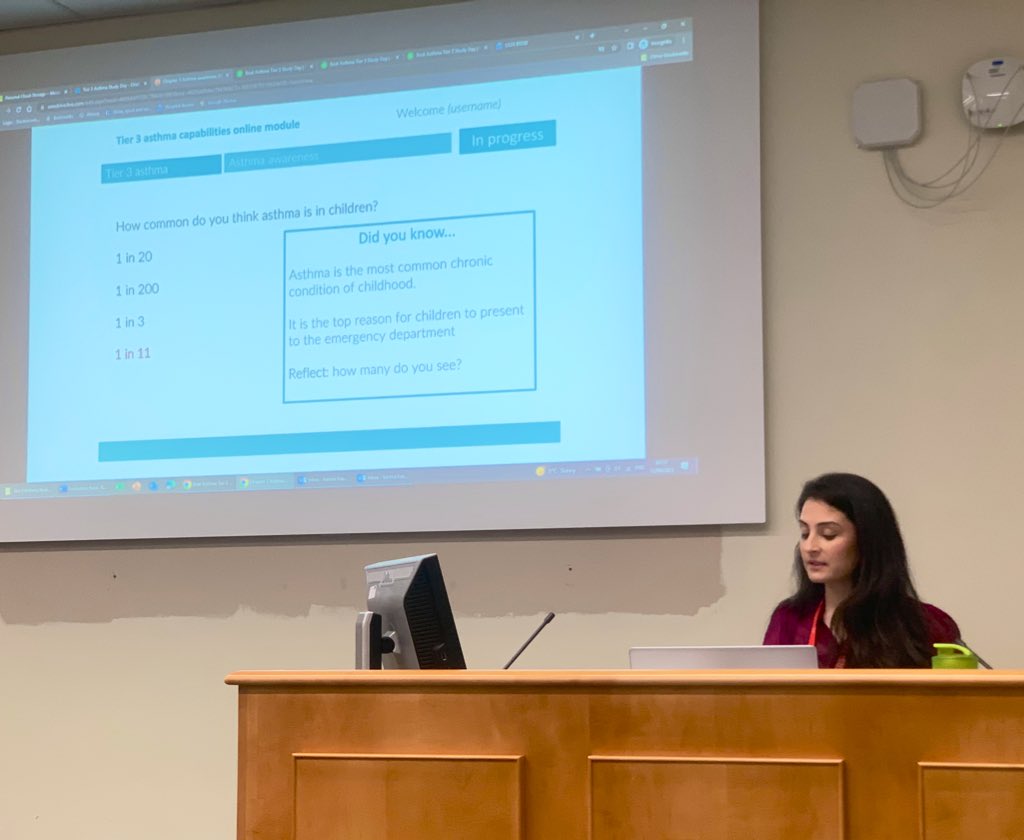

With the UK having one of the highest mortality rates in Europe in CYP with asthma, Dr Mark L Levy will be joining us to further shed light on how we can tackle this largely preventable issue #paedresp2024 #asthma